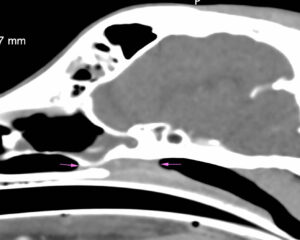

Radiología intraoral: una herramienta imprescindible en odontología veterinaria

Esta técnica contribuye a la evaluación diagnóstica y permite aplicar tratamientos, prevenir complicaciones, realizar seguimientos terapéuticos y/o controles posquirúrgicos, evaluar la edad del paciente y obtener registros permanentes para su historia clínica y para futuras valoraciones.